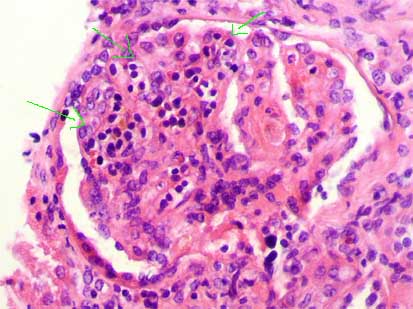

The characteristic histologic feature is sclerosis of segments of the glomerular tuft in some glomeruli (“segmental and focal”), with mesangial expansion and capillary lumen loss in these segments. The injury can be more notorious in the vascular pole or in the periphery of the tuft. When advancing the process the sclerosis becomes global and is indistinguishable of the secondary sclerosis to other diseases. The sclerosing segments are positive with PAS and silver-methenamine stains (type IV collagen). From the Fifties it is said that juxtamedullary glomeruli are more compromised by the segmental lesions. There are, in many cases, podocyte hypertrophy and hyperplasia, mainly on the surface of the sclerosed tuft segment (“cap lesion” or “cellular lesion”). Podocytes frequently appear with protein droplets and lipid resorption. The glomeruli without sclerosing lesions can appear normal or with increase of the mesangial cellularity and, sometimes, hypertrophic (glomerulomegaly).

Figure 3. The hyaline segments are eosinophilic, with homogenous aspect (arrows); they are different to sclerosing segments, but they could correspond to lesions in different stage of evolution. (H&E, X400).

Figure 4. Segmental Hyalinosis with lipid vacuoles and reddish color with the trichrome stain (arrow). The adjacent tuft presents solidification, with diminution or loss of capillary lumens. (Mason’s trichrome, X400).